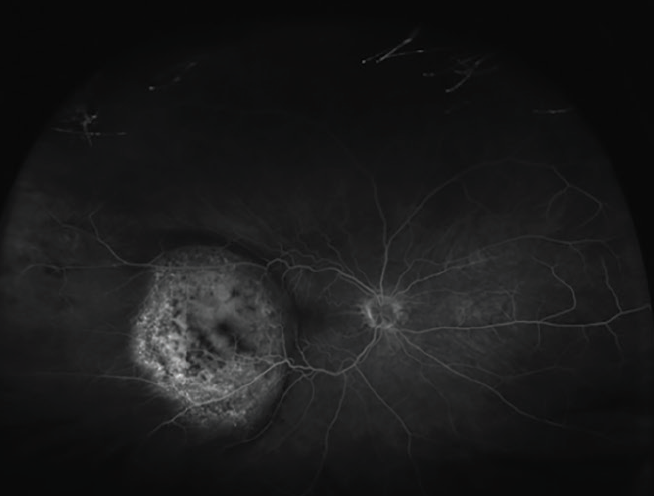

Ocular ultrasound demonstrated a significant decrease in the size of the choroidal mass and elevation of the retina (Figure 5).

<p>Figure 5. Ocular ultrasound shows decreased elevation of choroidal mass.</p>

Figure 5. Ocular ultrasound shows decreased elevation of choroidal mass.